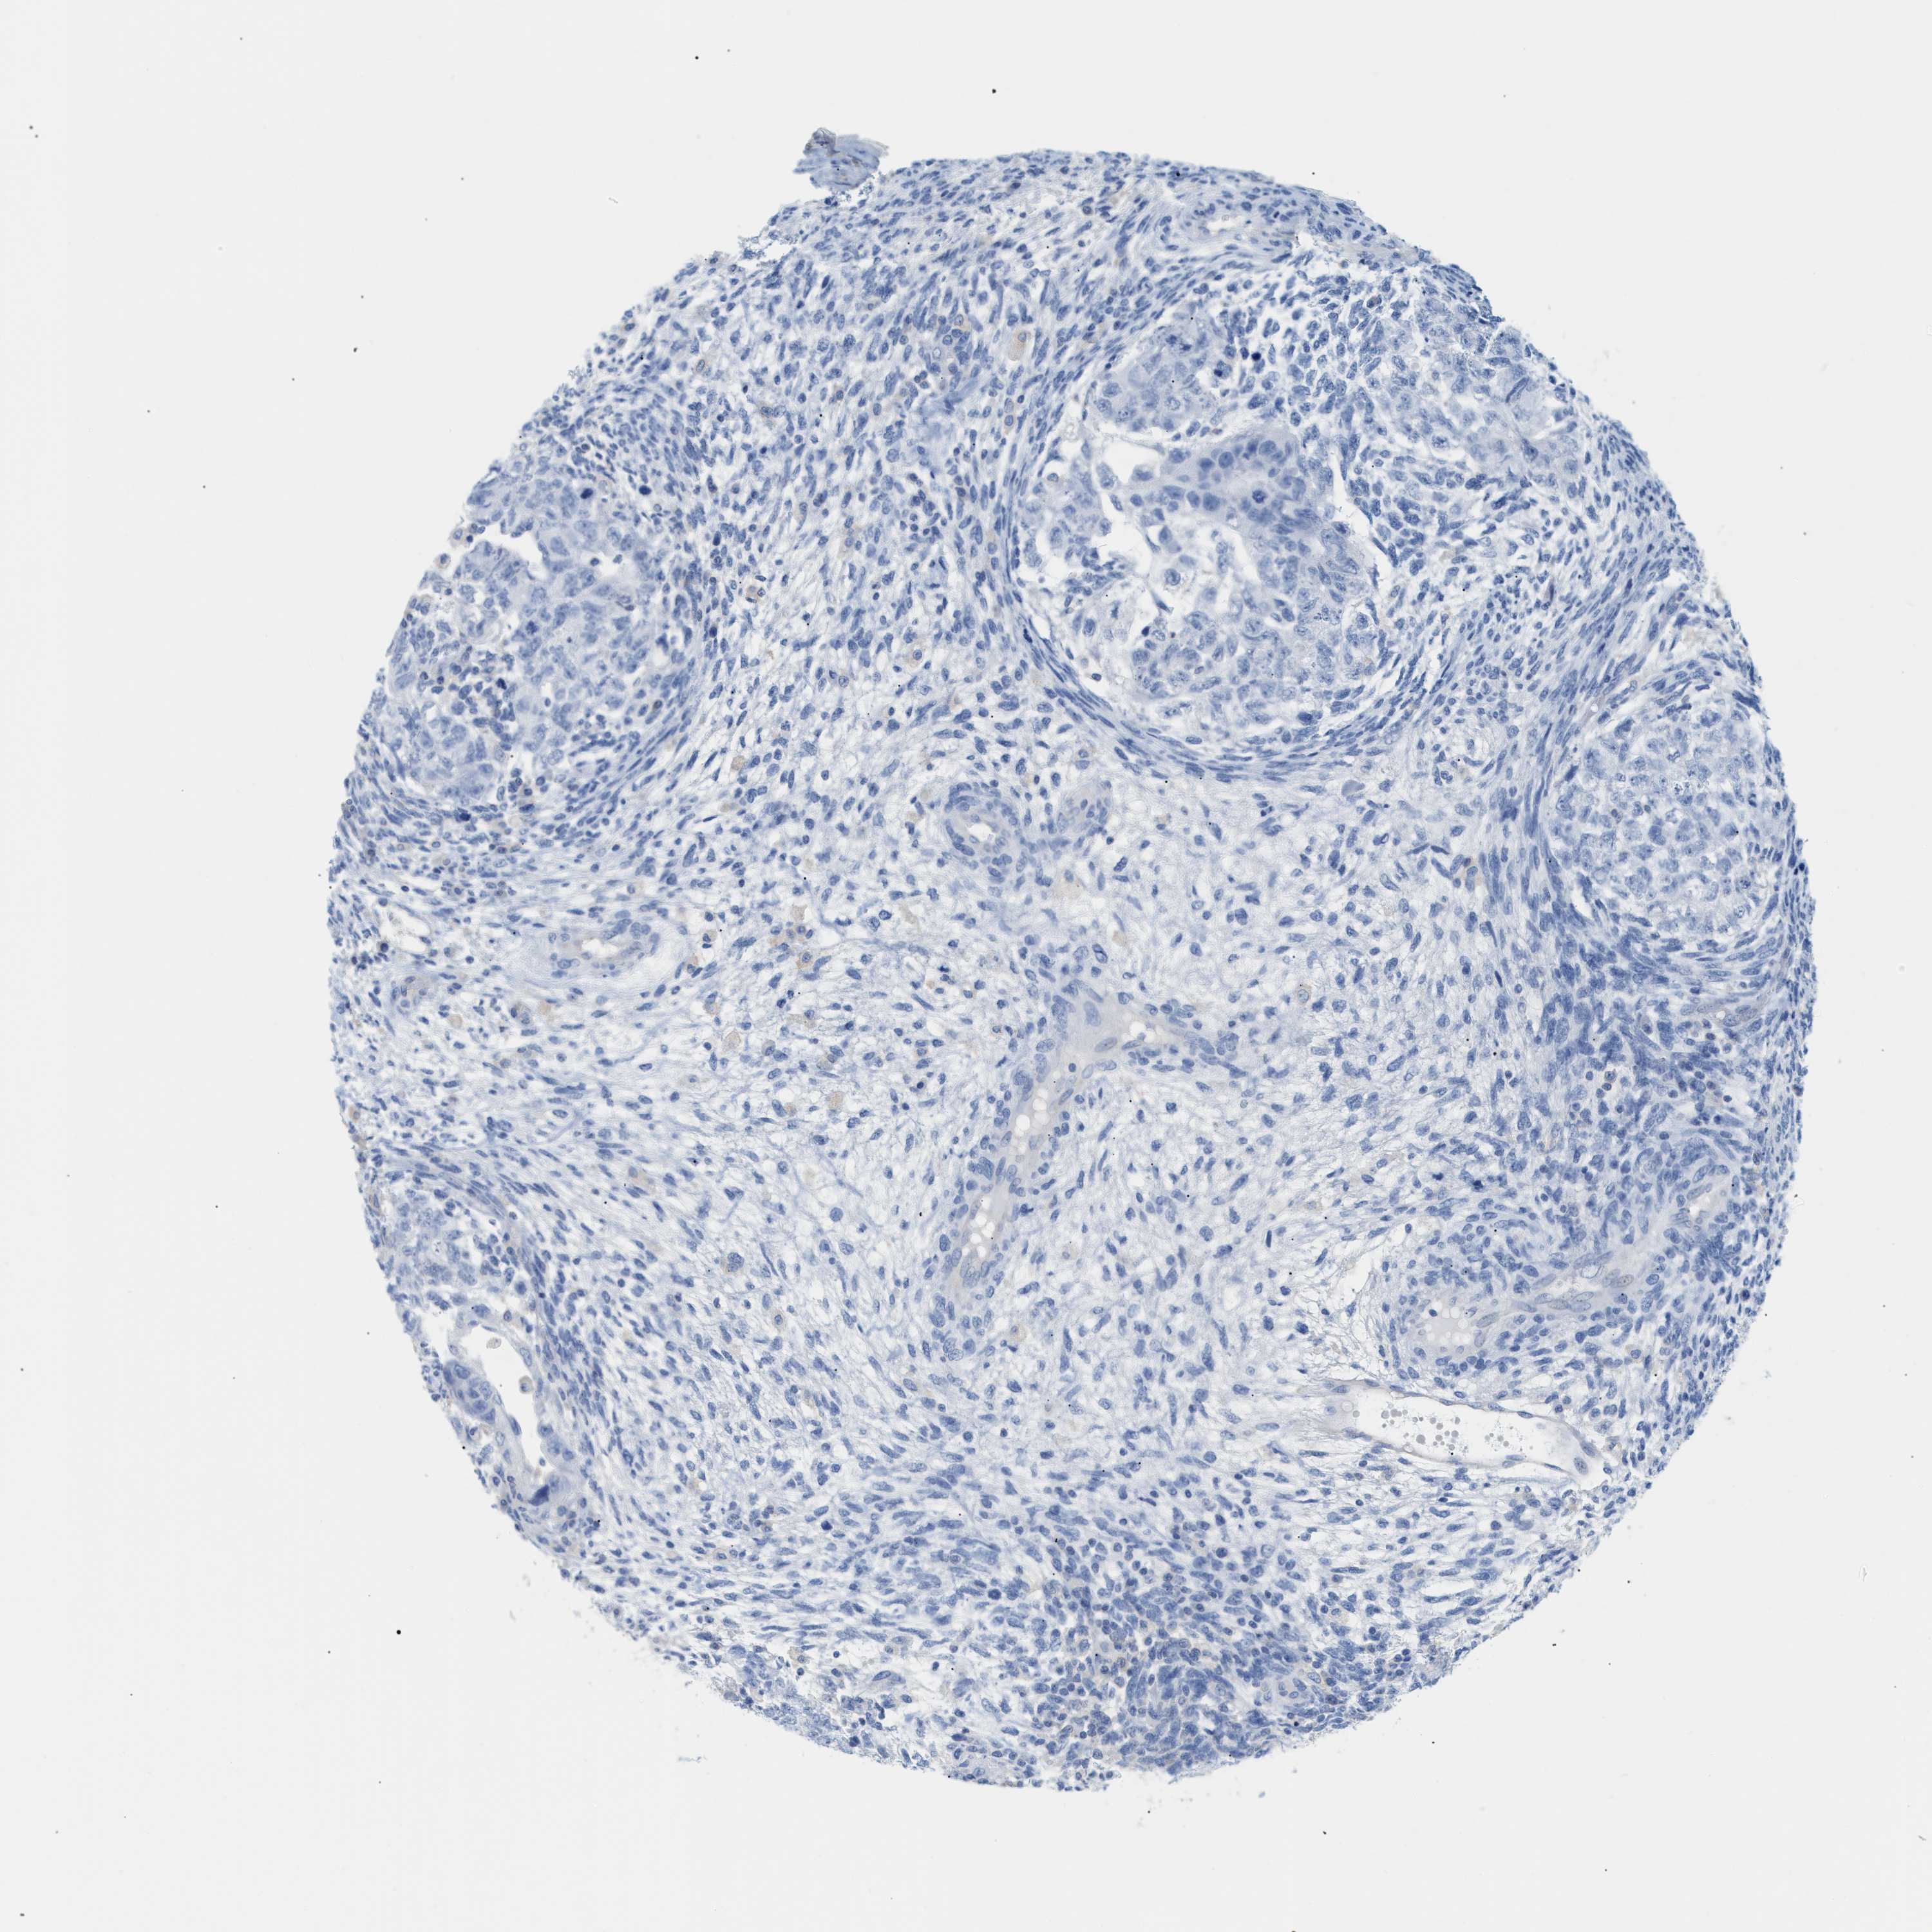

TESTIS CANCER - Protein expressioni

A mouse-over function shows sample information and annotation data. Click on an image to view it in a full screen mode. Samples can be filtered based on level of antibody staining by selecting one or several of the following categories: high, medium, low and not detected. The assay and annotation is described here.

Note that samples used for immunohistochemistry by the Human Protein Atlas do not correspond to samples in the TCGA dataset.

Antibody stainingi

Antibody staining in the annotated cell types in the current human tissue is reported as not detected, low, medium, or high, based on conventional immunohistochemistry profiling in selected tissues. This score is based on the combination of the staining intensity and fraction of stained cells.

Each image is clickable and will lead to virtual microscopy that enables deeper exploration of all samples and also displays staining intensity scores, fraction scores and subcellular localization as well as patient and tissue information for each sample.

Antibody HPA001667

Carcinoma, Embryonal, NOS

Seminoma, NOS